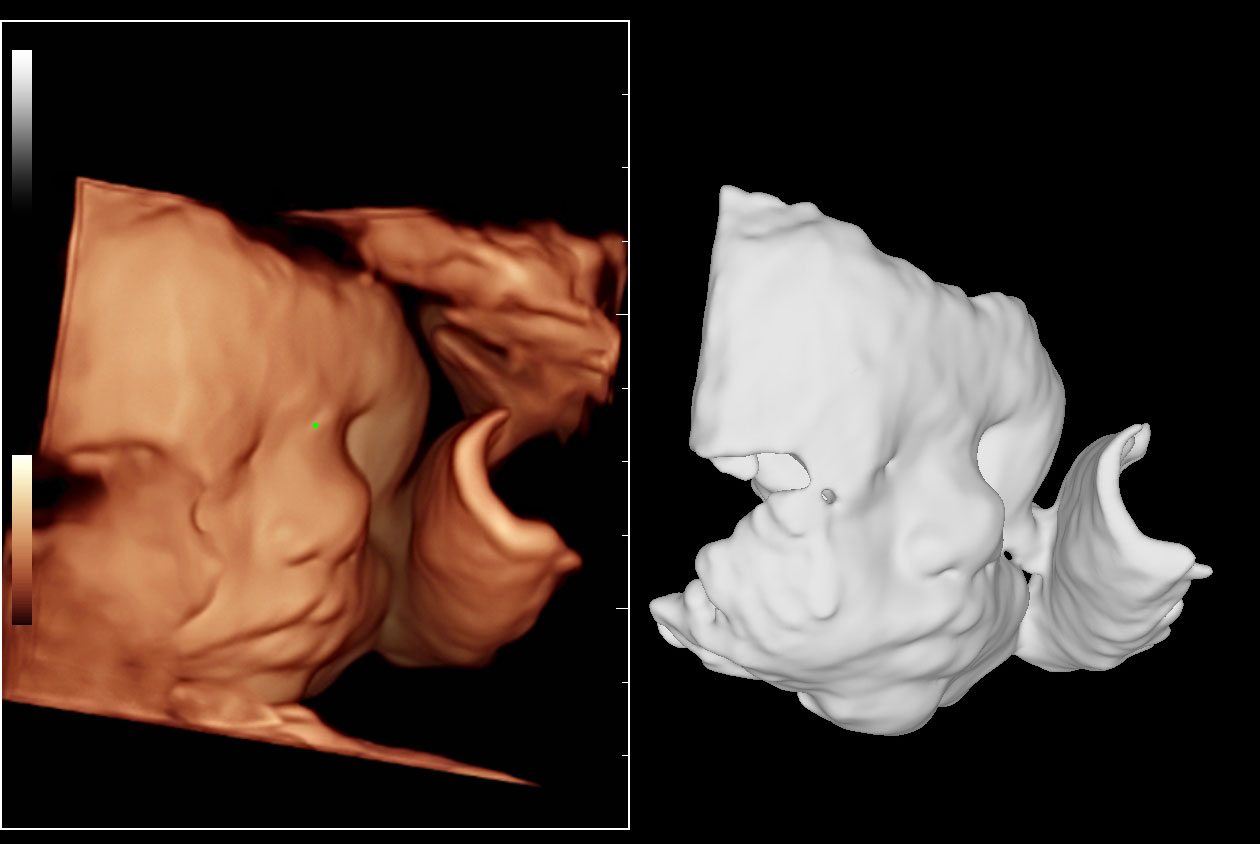

Women's Health | Radiology | Cardiovascular Imaging

Advanced Technologies

Enhancing Clinical Certainty

Clinical Images